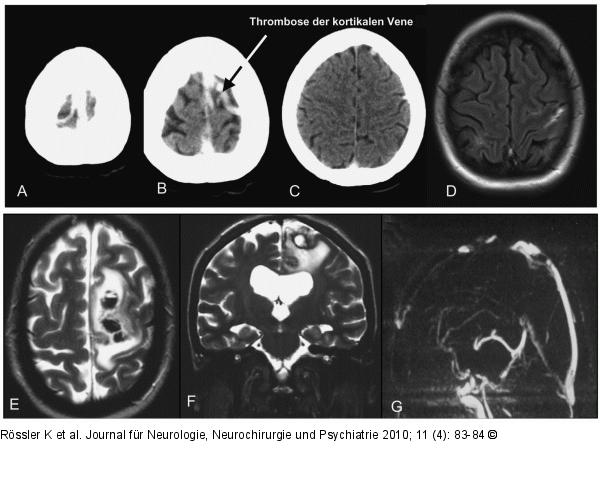

Abbildung 2: Grand-mal-Anfall

Präoperative MRT, T2, axial, ausgedehntes perifokales Ödem. |